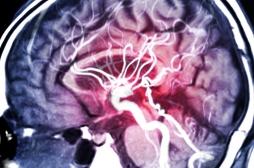

AVC

LES MALADIES